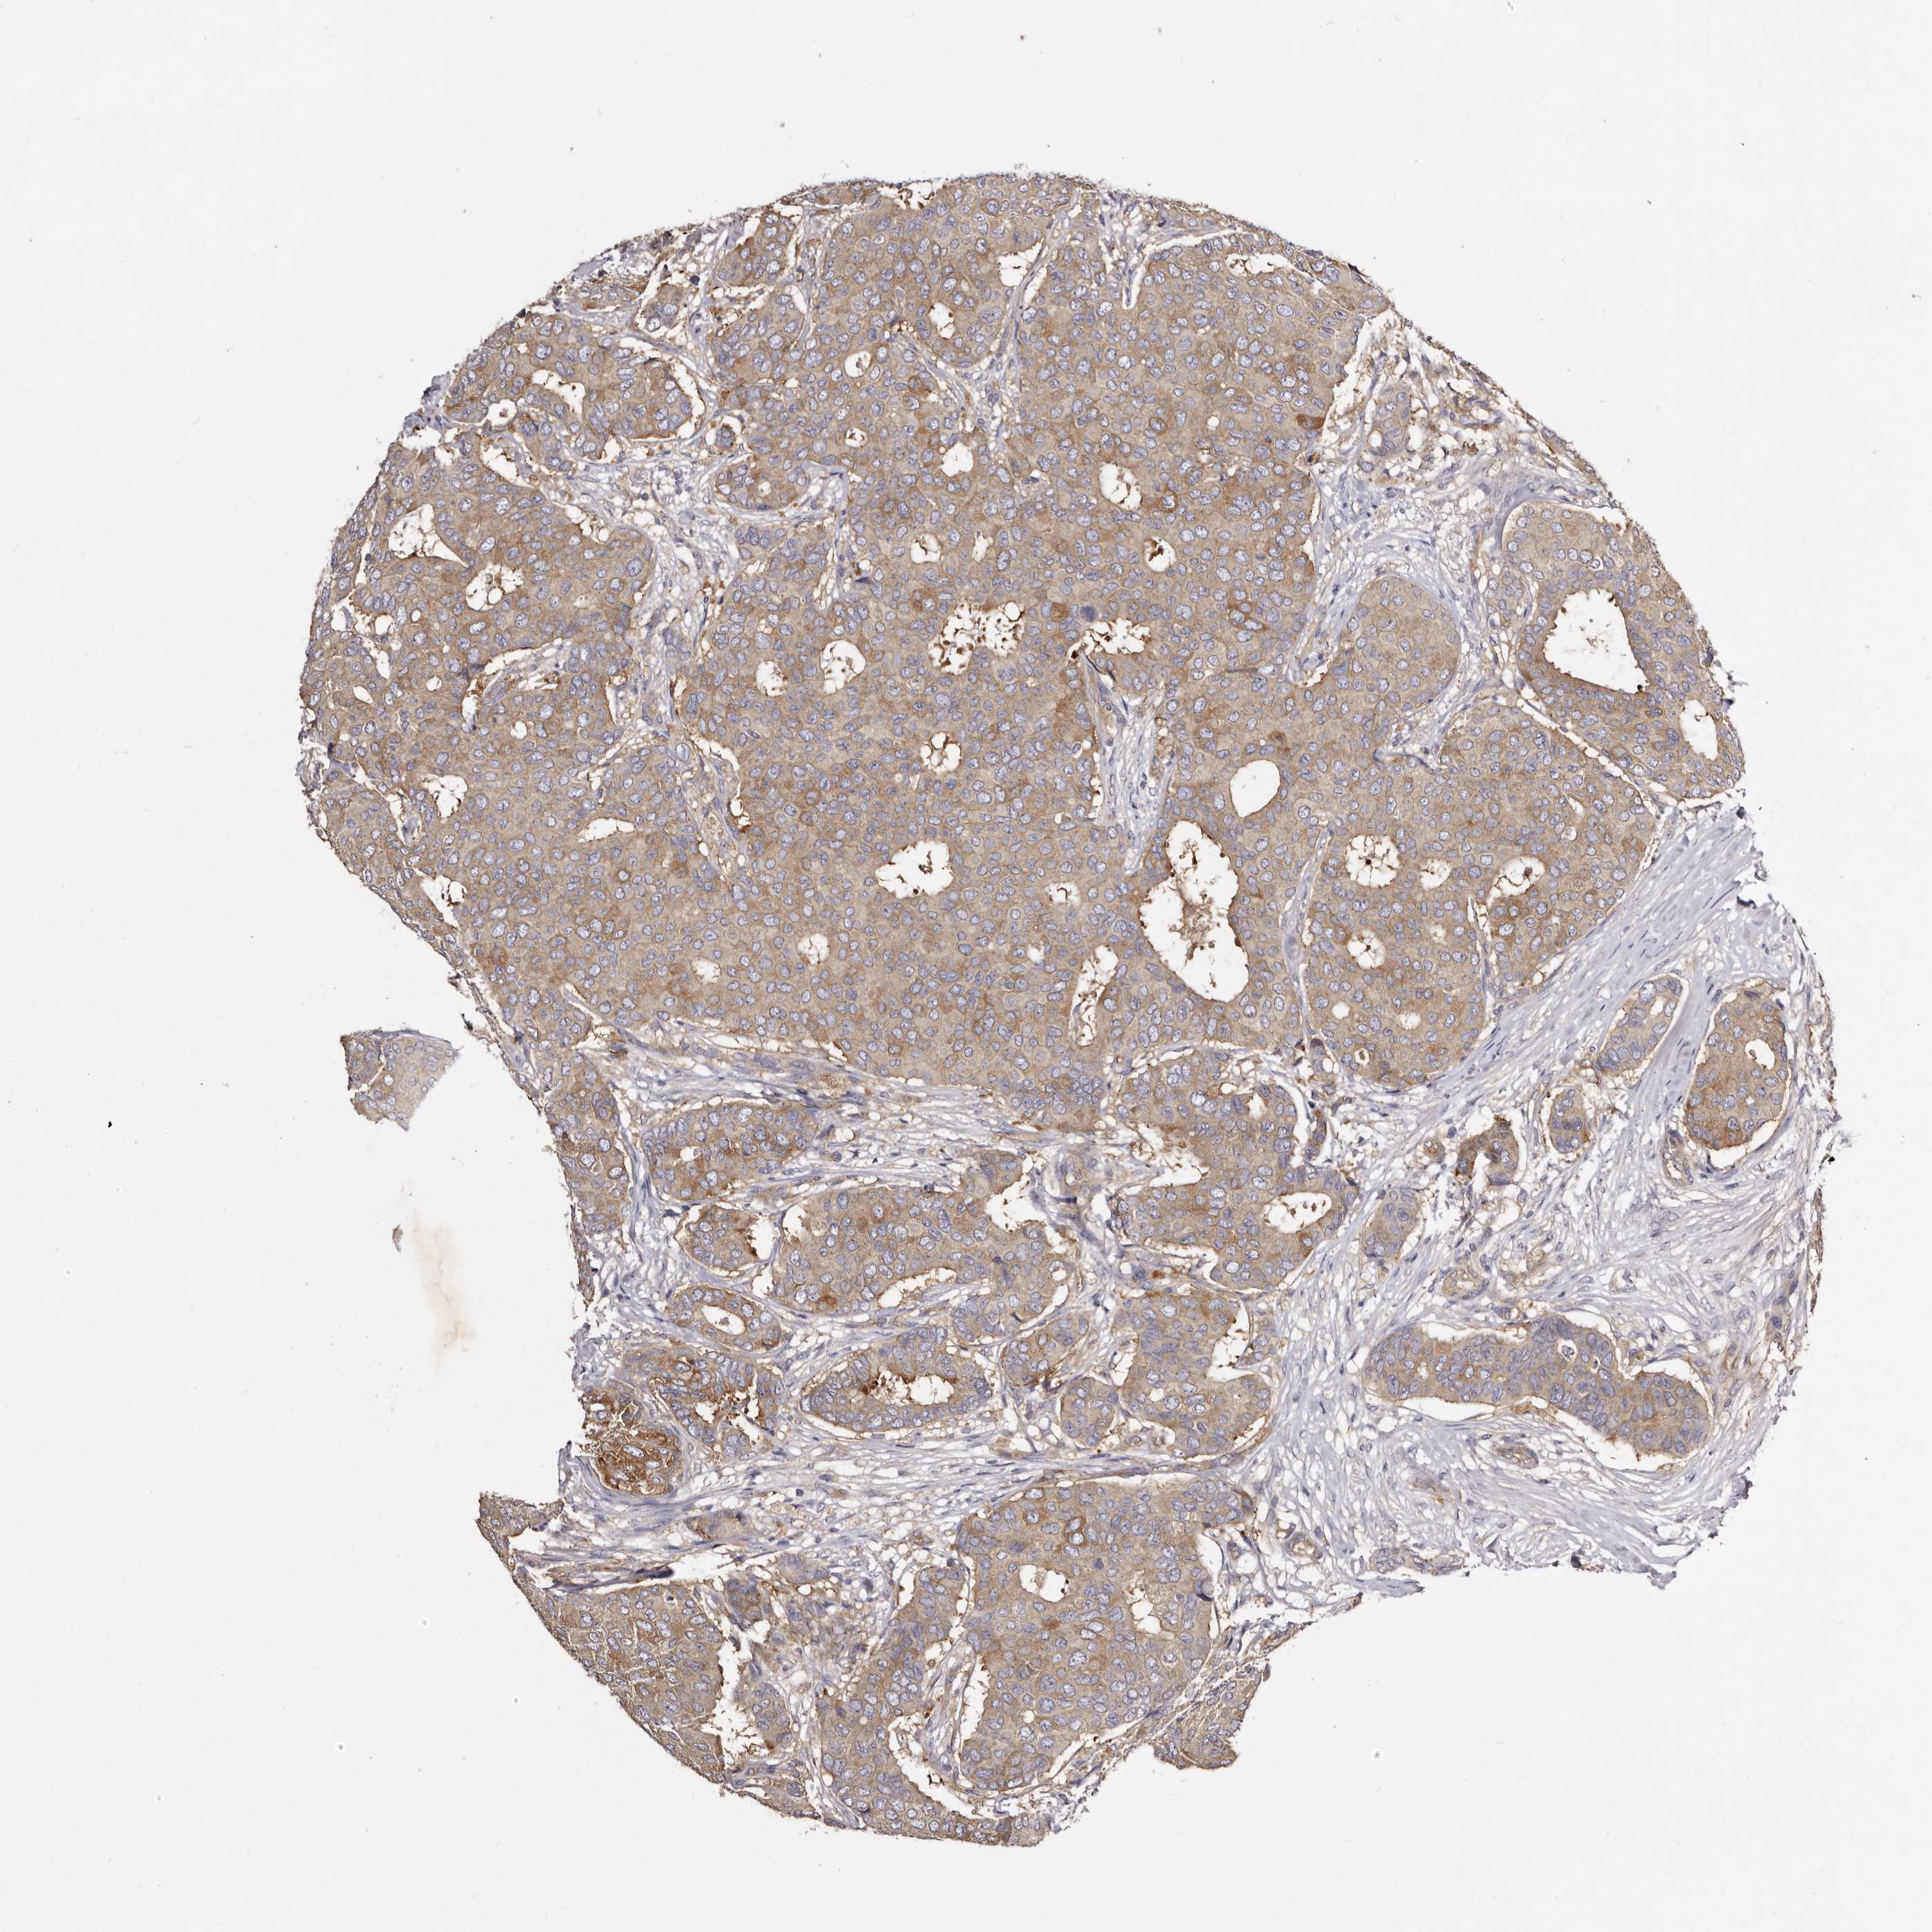

BRCA TCGA BRCA VALIDATION PROTEIN EXPRESSION

Breast cancer

Human cancer